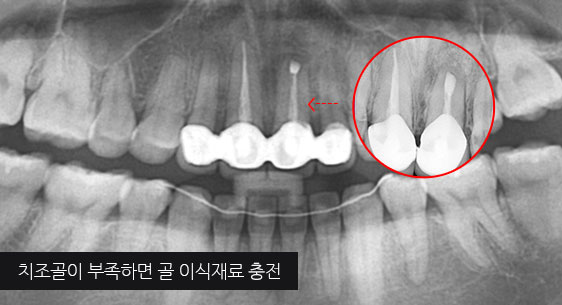

대부분의 치과에선 빼야하는 치아가 있거나 이미 빠졌거나, 신경 치료 후 예후 불량으로 인해 치아를 살릴 수 없는 경우 임플란트를 먼저 고려합니다. 고운미소치과는 인접치아를 움직여 그 공간을 닫아 임플란트 수술이나 보철 치료 없이 자연치를 최대한 활용하는 치료 계획을 세웁니다.

치조골 손상이 심해 발치를 하고 임플란트를 해야 하는 상황

인접치아로 발치된 공간을 메움

자연치보존 교정치료

46세 남성환자로 상악동 거상술과 임플란트 진단을 받은 상태로 내원. 치조골이 2/3이상 오염되어살릴 수 없어 발치를 진행, 인접치아를 움직여 발치 된 공간을 닫는 교정치료를 시행하였습니다.